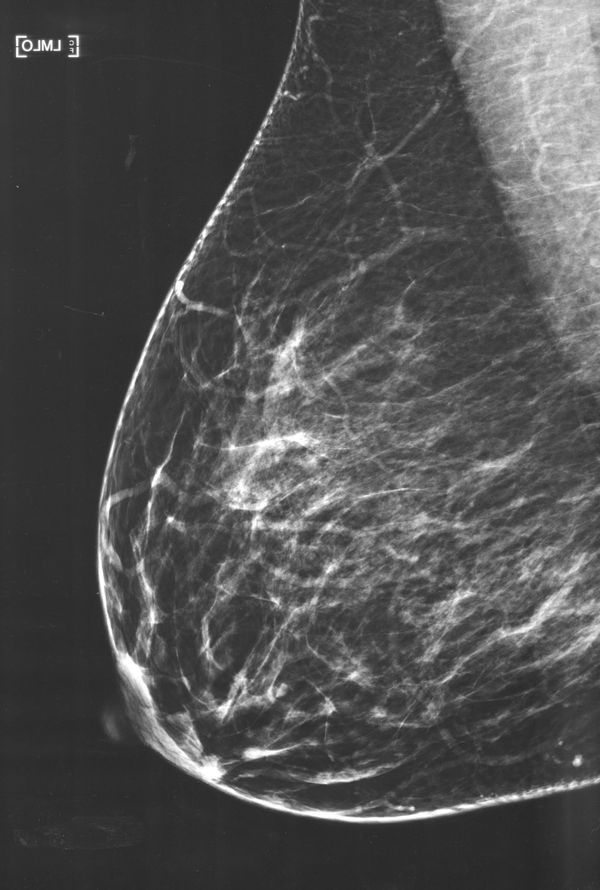

"Mleko" (2021-2024) is a visual research project born from my fascination with human milk and its intricate nature. Following the birth of my first child in 2021, I was captivated by this biological substance uniquely tailored to nourish my son. This curiosity propelled me to delve deeper into the multifaceted dimensions of human milk and the experience of breastfeeding.

In “Mothers; An Essay on Love and Cruelty”, Jacqueline Rose writes that; “The supreme symbol of mother love is, of course, the breast, which reappears in modern discussions of motherhood”, which makes the subject of breastfeeding central and opinionated. Milk is breaching a gap between milk giver and child, between an animal and human, between self and other, between myth and world.

Through a blend of photography, text, video, and audio interviews, "Mleko" aims to demystify human milk, encouraging open dialogue and reducing the stigma associated with breastfeeding in both public and private spheres.